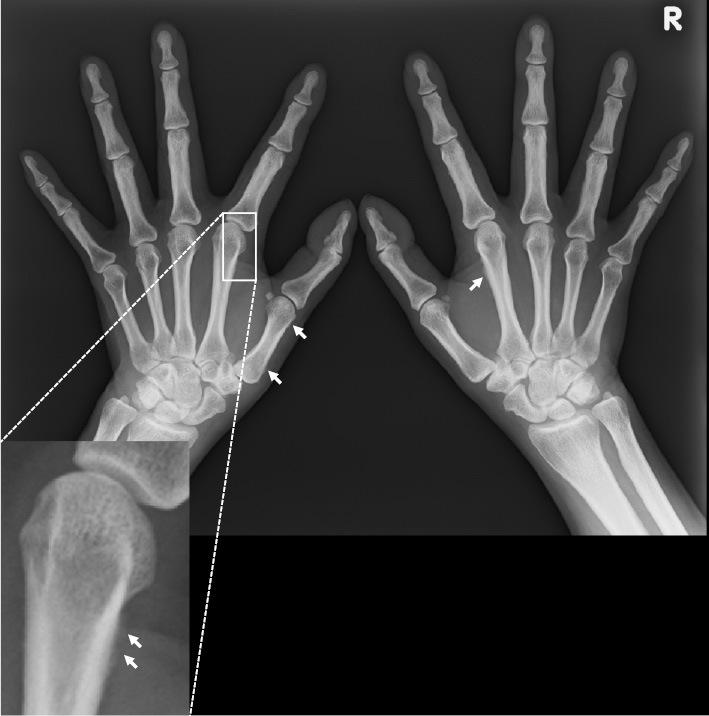

Musculoskeletal Ultrasound Manifestation of Osteoarthropathy in EMO Syndrome.

Intern Med. 2022 Jan 15;61(2):273-274. doi: 10.2169/internalmedicine.7106-21. Epub 2021 Jul 30.

DOI:10.2169/internalmedicine.7106-21

PMID:34334562

Musculoskeletal Ultrasound Manifestation of Osteoarthropathy in EMO Syndrome.EMO综合征中骨关节炎的肌肉骨骼超声表现